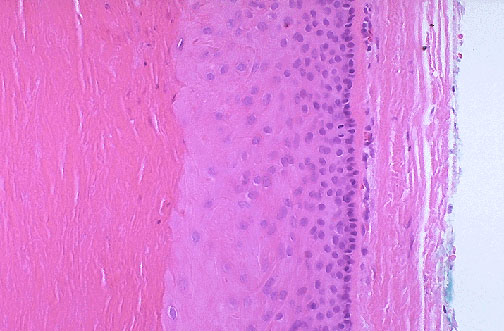

| This is an epidermal inclusion cyst excised from beneath the skin surface, with a rim of dermal connective tissue at the right. These cysts are seen most frequently on face, scalp, neck, and trunk. They are about 1 to 5 cm in size. They have a wall of epidermis that desquamates keratin, seen as the laminated pink material at the left here, which forms the soft cyst contents that give it characteristics which lead to the clinical description "sebaceous cyst". The cyst can rupture and lead to marked foreign body inflammation. |